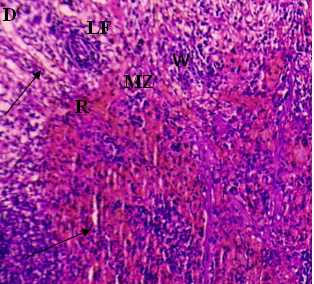

The current investigation focused on spleen histopathology to examine the overall condition of the organ. Elmore (2006), R. E. Mebius and G. Kraal (2005), as well as other sources, were used to anatomize the histopathological differences shown in fig. 114,15. Fig. 1 shows normal histoarchitecture in the control spleen tissue of a male albino rat, with sufficient amounts of red pulp (R), white pulp (W), lymphoid follicles (LF), and marginal zone (MZ). Table 2 has detailed histology observations. The histological structures in the cyphenothrin-treated group were well terminated, just like in the control group. The red pulp in the group that received high doses of the pesticide cyphenothrin showed decreased cellularity, while the white pulp was severely destroyed, with no normal lymphoid follicle and boundary zone. White pulp and red pulp from the low-cure cyphenothrin group showed destroyed cellular integrity. This cyphenothrin-treated group, which included high and low doses, demonstrated notable modifications of histological structures in contrast. In comparison to the cyphenothrin high dosage group, the white pulp recovered effectively in the cyphenothrin insecticide low dose treatment group.

Fig. 1: (A) and (B) Spleen sections of control rats: (R) red pulp; (W) white pulp; (LF) lymphoid follicle; (MZ) marginal zone; (PALS) Periarteriolar lymphoid sheath. H and E, x100. (C) and (D) Spleen structure of rat treated with cyphenothrin (63.6 mg/Kg BW) respectively: arrow head Show a thin damaged marginal zone (MZ), asterisk (*) indicates decreased cellularity (rarefication) and altered structural integrity of white pulp, H and E, 100×. (E) and (F) spleen tissues of cyphenothrin treated (35.33 mg/Kg BW) respectively: arrow shows damaged tissue region, marginal zone (MZ) and lymphoid follicles (LF). H and E, 100